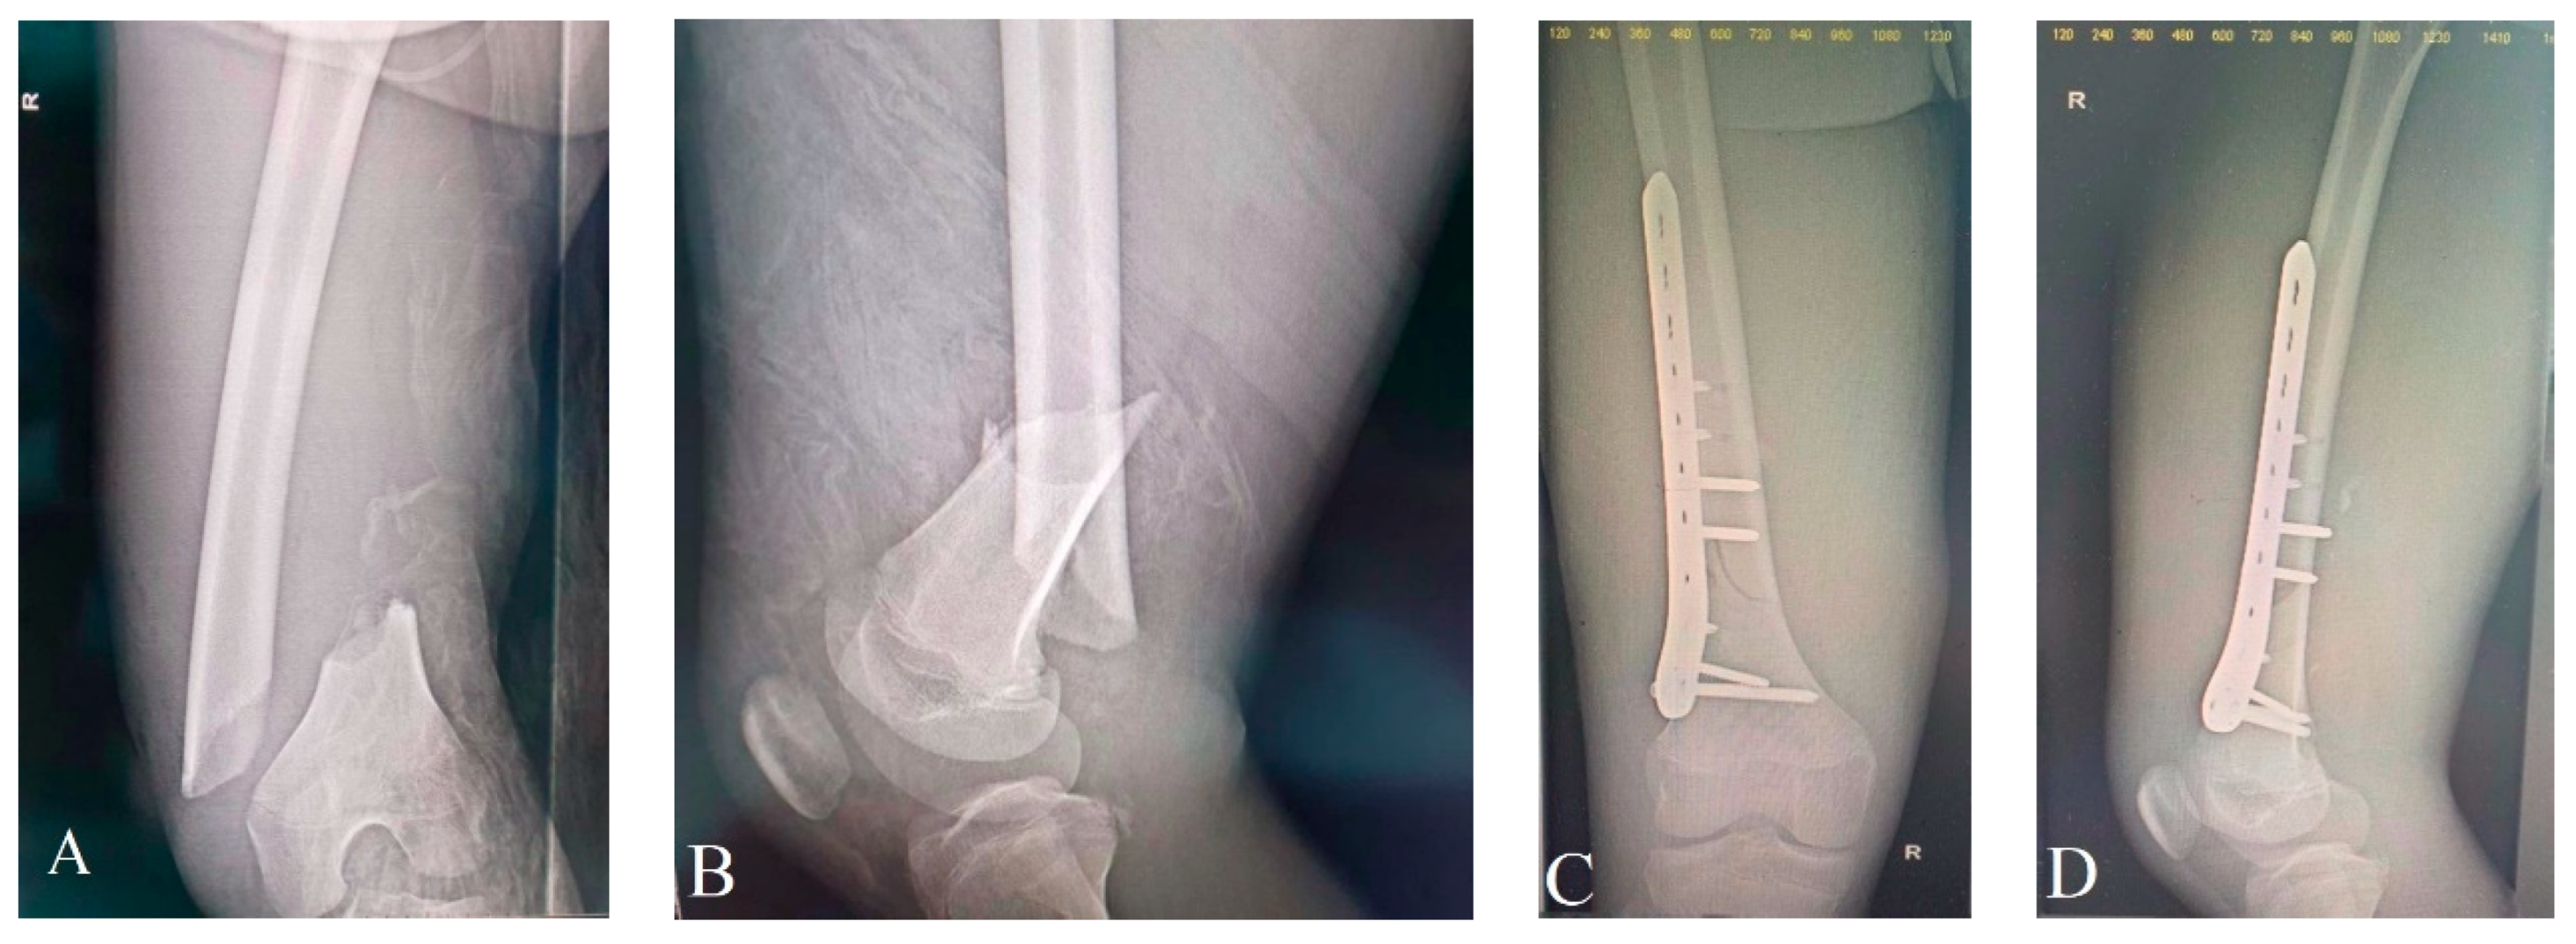

Open femur fractures are unusual and indicative of high-velocity trauma. They frequently come together with additional injuries, especially head trauma, and the child needs to be evaluated thoroughly to rule out these types of injuries [8,57,58]. In the instance of resuscitation, external fixation of the fractured femur is becoming more frequently utilized as a preventative approach [59]. Debridement of an open femoral fracture is identical to that among all open fractures. In the majority of instances, thigh muscles offer sufficient protection, and surgical treatment is scarcely required. The fracture is definitively fixed immediately when the child is secure. According to the patient’s age, fracture setting, accessible resources, and level of competence, there exists several treatment options, such as maintaining external fixation, switching to internal fixation using a plate (Figure 3), or ESIN [57,60,61,62]. When employed as the final option, external fixators have been linked with greater risks compared to alternative forms of fixation [57,61]. Open femoral fractures managed by external fixation required additional time to heal compared to alternative approaches, according to Hutchins et al. [57]. Fracture-related risks lengthened the duration required for fracture repair. Fifty percent of fractures in their cohort acquired osteomyelitis and twenty percent were malunited, making grade III fractures particularly challenging to treat. Intramedullary fixation is acquiring recognition in age-appropriate populations [30].

Figure 3. Fifteen-year-old boy involved in a car accident (pedestrian) who suffered a Gustilo–Anderson type I right distal femur fracture, picture (A,B), which was surgically resolved by open reduction and osteosynthesis with a distal locked femoral plate picture (C,D) at “St. Mary’s” Clinical Emergency Hospital for Children, Iași, Romania, Pediatric Orthopedics Department.